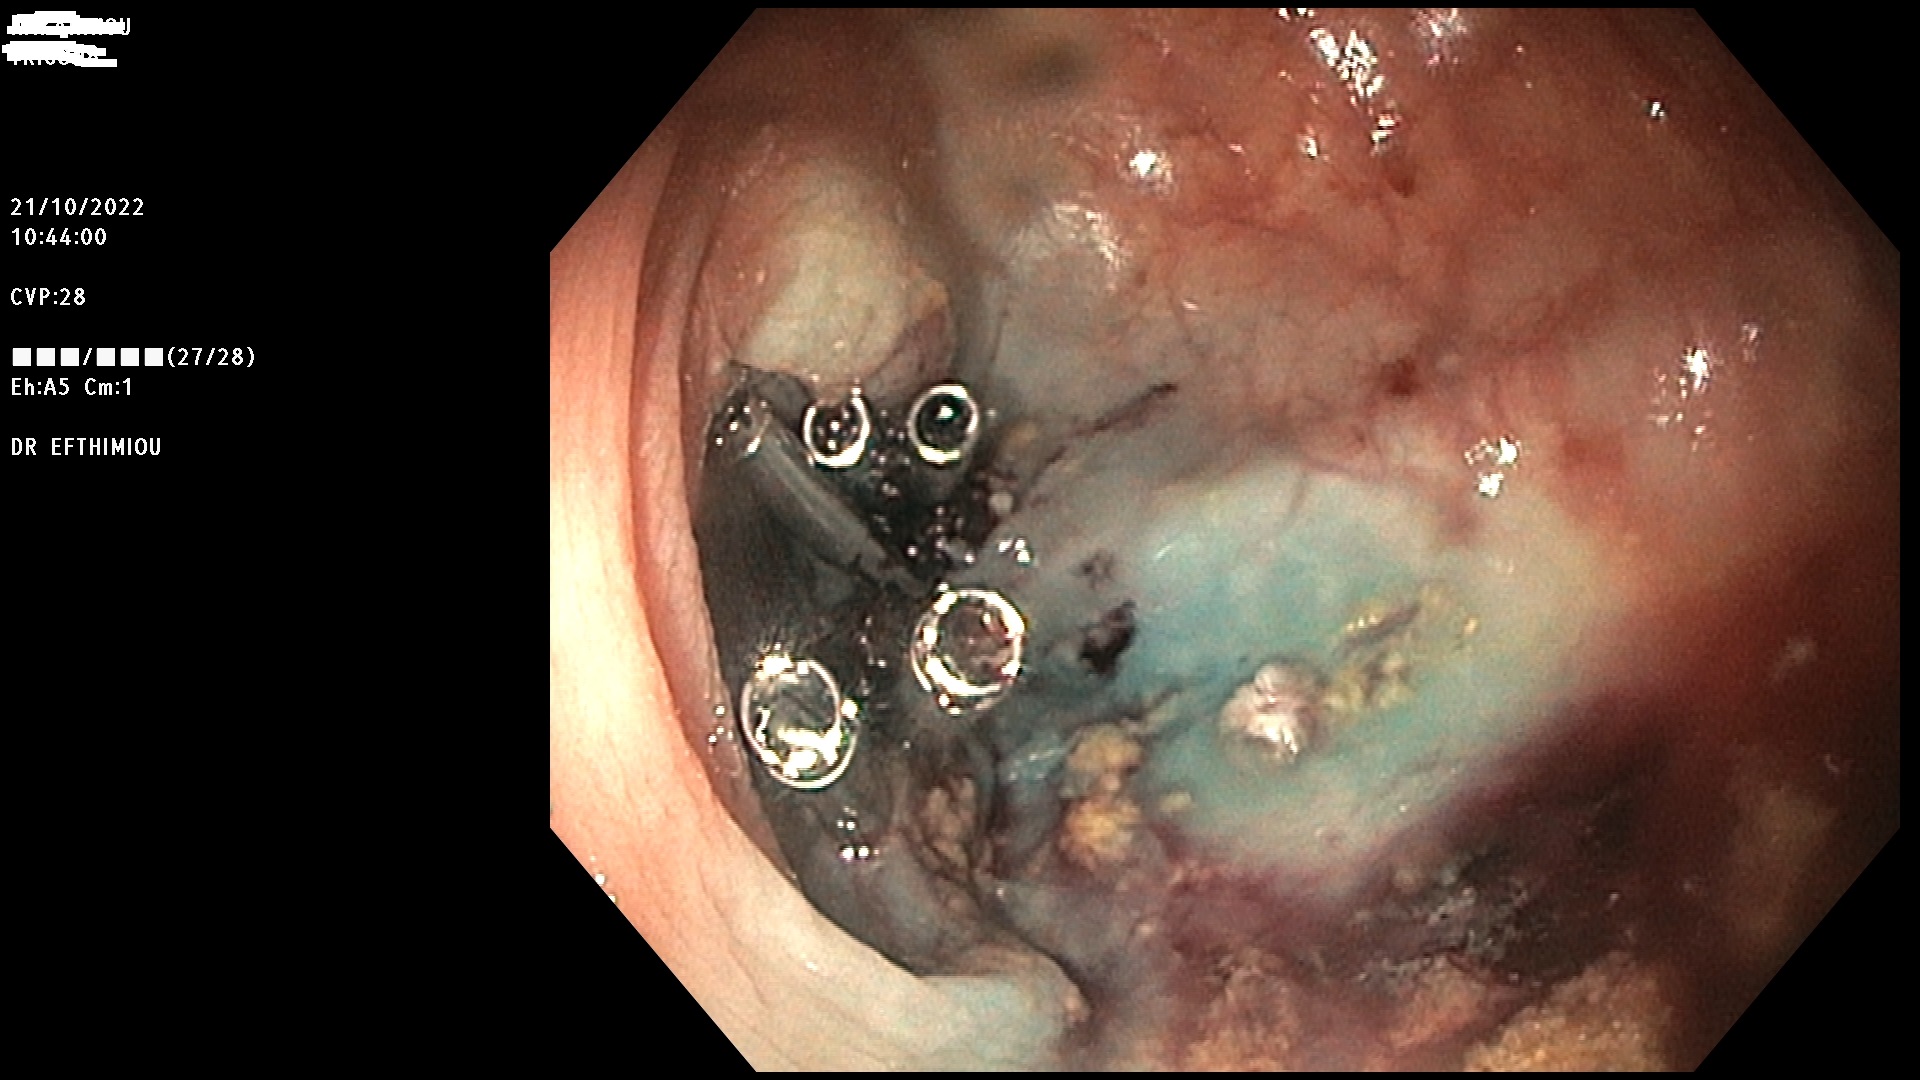

Η επέμβαση γίνεται κατά τη διάρκεια της κολονοσκόπησης με τη χρήση

διαφόρων εργαλείων (λαβίδες, βελόνες υποβλεννογόνιας έγχυσης, βρόχοι

διαθερμίας, ψυχροί βρόχοι, endoloops, κ.ά.) ανάλογα με το μέγεθος, τη

μορφολογία και την εντόπιση του πολύποδα (Εικόνες 1-3). Ο ασθενής

βρίσκεται σε ήπια καταστολή («μέθη») και δεν αισθάνεται καθόλου πόνο.